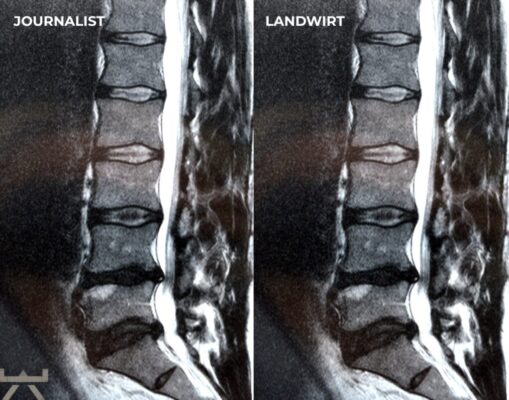

Viele machen ihre Arbeit oder ihren Sport für Arthrose verantwortlich, obwohl die meisten Forschungsergebnisse feststellen, dass unsere beruflichen und freizeitlichen Aktivitäten einen relativ geringen Einfluss auf strukturelle Veränderungen haben. Eine der interessantesten Möglichkeiten, dies zu demonstrieren, sind MRT-Studien an schmerzfreien genetisch eineiigen Zwillingen, die aber sehr unterschiedliche berufliche und freizeitliche Aktivitätsniveaus haben, und trotzdem sehr ähnlich aussehende Scans aufweisen. Studien zeigen uns diesbezüglich, dass eine Wirbelsäule, die den größten Teil des Tages sitzt, jener bemerkenswert ähnlichsieht, welche den ganzen Tag schwere Arbeit leisten muss. 11